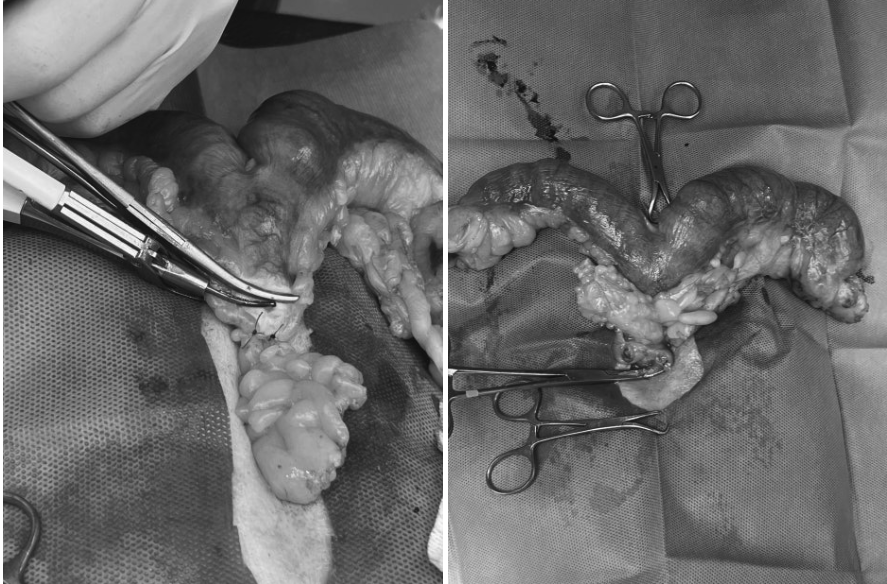

라온동물메디컬센터에서는 자궁축농증의 원인이 되는 난소와 염증이 가득 찬 자궁 전체를 제거하는 수술을 계획했습니다. ㅋㅈ는 수술 전 충분한 수액 처치와 전신 상태 안정화를 시행한 후 전신 마취 하에 자궁 및 난소 적출술(Ovariohysterectomy) 을 진행하였습니다.

환자 수술사진 / 출처: 라온동물메디컬센터

염증이 심한 자궁은 매우 취약하기 때문에 수술 중 파열 위험을 최소화하며, 주변 조직 손상을 줄이는 방향으로 신중하게 수술을완료하였습니다.